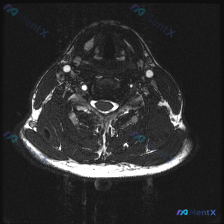

这是一张颈椎下段(推测C5-C6或C6-C7椎间盘水平)的T2轴位MRI,我们先读片:

- 脊髓:信号均匀,没有明显异常高信号水肿或低信号出血,形态正常

- 脑脊液:T2高信号清晰,轮廓正常

- 椎间盘与椎体:椎间盘后缘形态正常,没有明显后突,椎体骨髓信号没有异常

- 硬膜囊与神经根:硬膜囊没有受压变形,两侧神经根出口走形清晰,没有狭窄

- 椎旁软组织与骨性结构:甲状腺、气管、血管、肌肉位置信号都正常,椎板等附件结构也没有明显异常

这张图像整体评估下来,本层面没有发现明显的占位、炎症、严重退变、椎间盘突出或者椎管狭窄,也没有需要紧急处理的红旗征象。核心问题来了:临床提示考虑椎间盘病变,但这张单层面图像没有发现异常,该怎么分析?